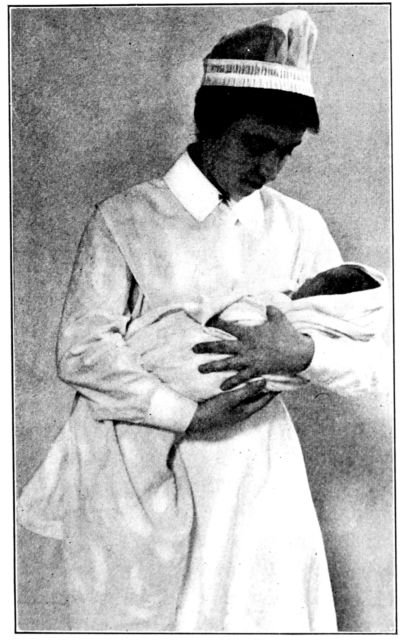

| 167. | Proper method of carrying baby | 487 |